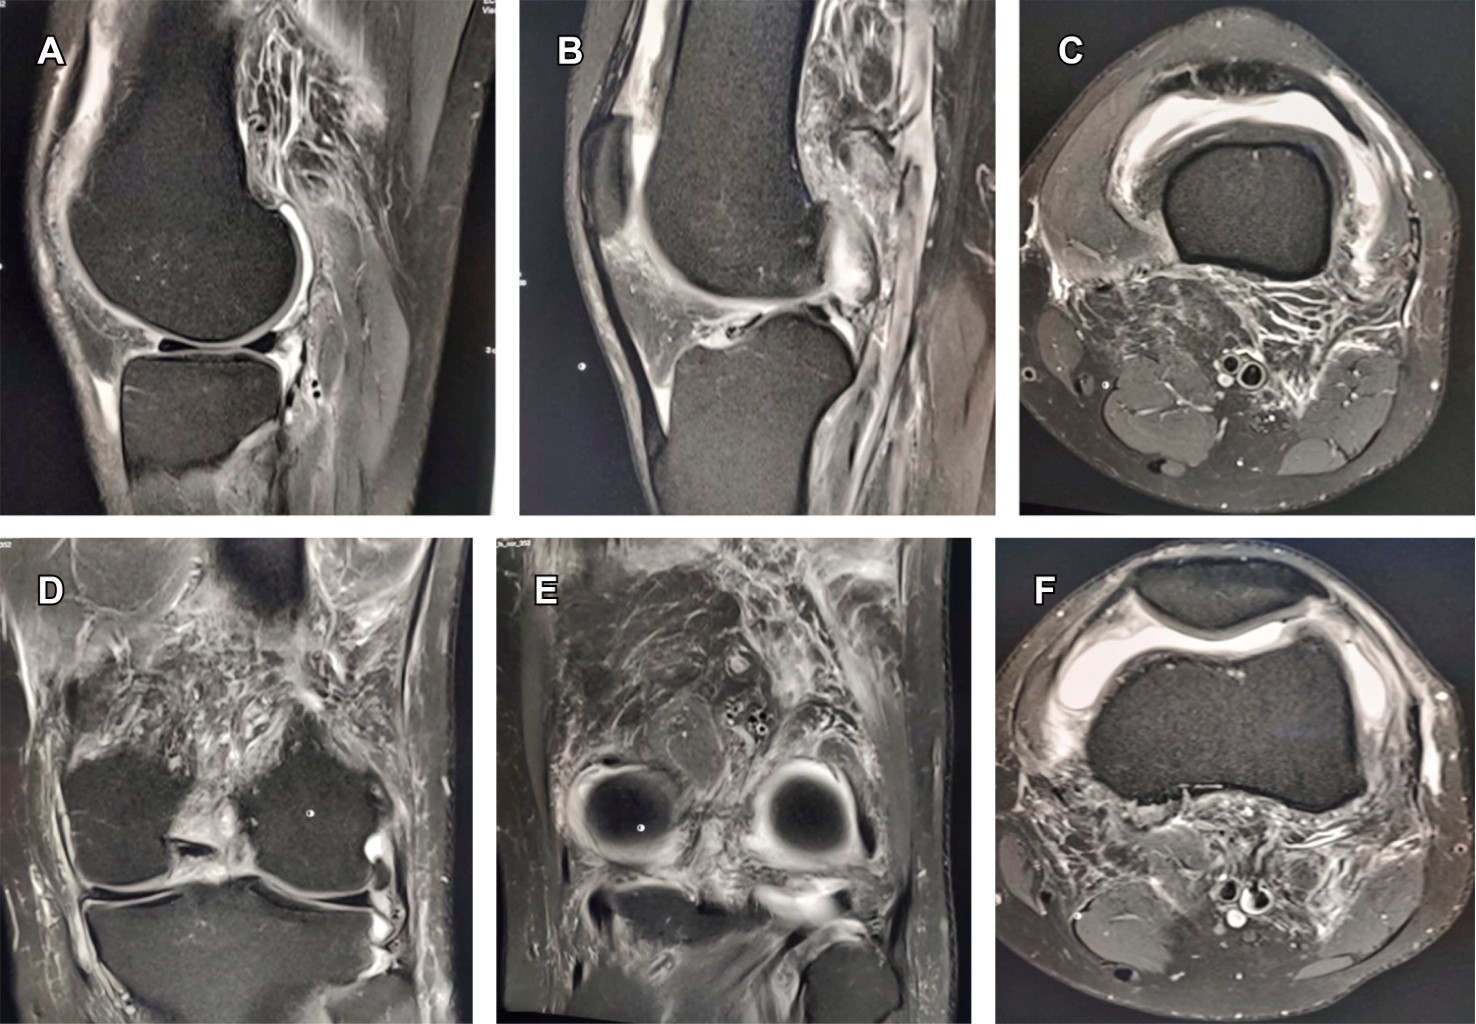

Paciente masculino de 33 años, con sintomatología caracterizada por edema de rodilla derecha, dolor en 5/10 en la escala visual analógica (EVA) y flexo-extensión limitada de un año de evolución; se le realizó resonancia magnética (RM), en la que se mostró: derrame articular, hiperplasia sinovial con formación de nódulos por acumulación de hemosiderina, lo que originó artefactos parecidos a flores en botón (blooming en idioma inglés) en las imágenes T2 y Short T inversion Recovery (STIR) (Figura 1), se presenta erosión en el cóndilo femoral lateral y zonas de intensidad variable. Se efectuó punción articular que mostró líquido serohemático. Por las características de imagen en la RM, se llevó a cabo el diagnóstico de sinovitis villonodular pigmentada difusa (SVPD) contra el diagnóstico de tumor de células gigantes en rodilla derecha; no obstante, la biopsia confirmó SVPD.

Figura 1